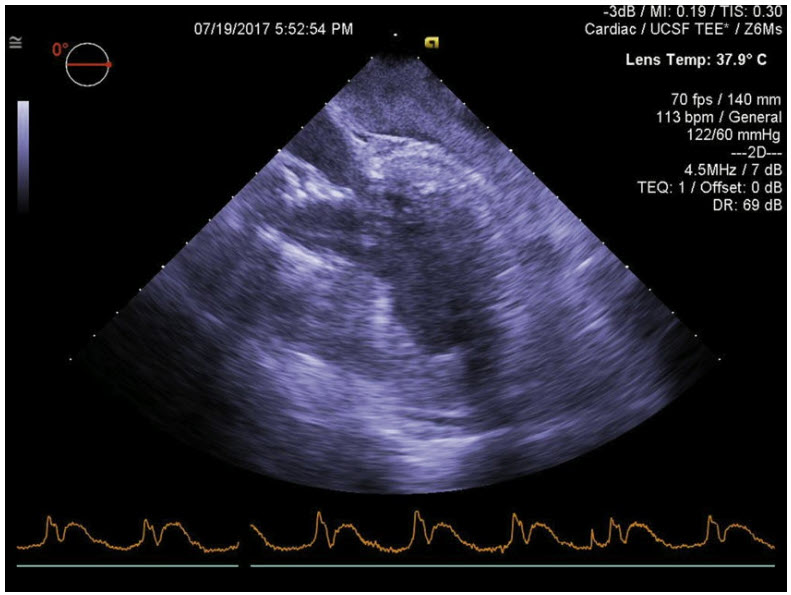

An 85-year-old woman underwent a transapical transcatheter aortic valve replacement (TAVR) for severe symptomatic aortic stenosis. After an uneventful procedure, she is brought to the ICU intubated and sedated. In the 30 minutes after arrival to the ICU she develops progressive tachycardia and hypotension, which prompts the placement of a TEE probe. The mid-esophageal 4-chamber view is shown in the figure below:

Based on the findings in the image, what is the most appropriate next step in management?

A. Left-sided chest tube placement

B. Emergent surgical pericardial evacuation

C. Pericardial drain placement

D. CT angiography of the chest